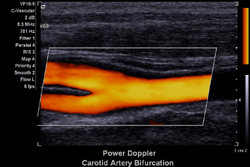

Ecodoppler Colorido de Carótidas

• from Heart Attack News

• Julho, 2010

Demonstração de exame de carótidas.